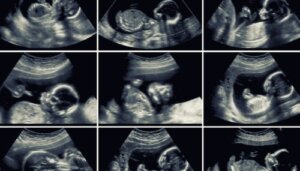

20-ukers ultralyd er en rutinetest som tillater en grundig evaluering av babyens organer, mors livmor og morkaken. I tillegg til den verdifulle informasjonen den tilbyr, utføres den på et nøkkeløyeblikk i svangerskapet.

Generelt er denne ultralyden 2D, men hvis enheten tillater det, kan noen bilder tas i 3D eller 4D. Sistnevnte viser babyens ansiktstrekk med større presisjon og viser til og med bevegelsene deres i sanntid.

Spesialisten kan kombinere 2D- og 3D-bilder for en mer fullstendig analyse av alle babyens strukturer.